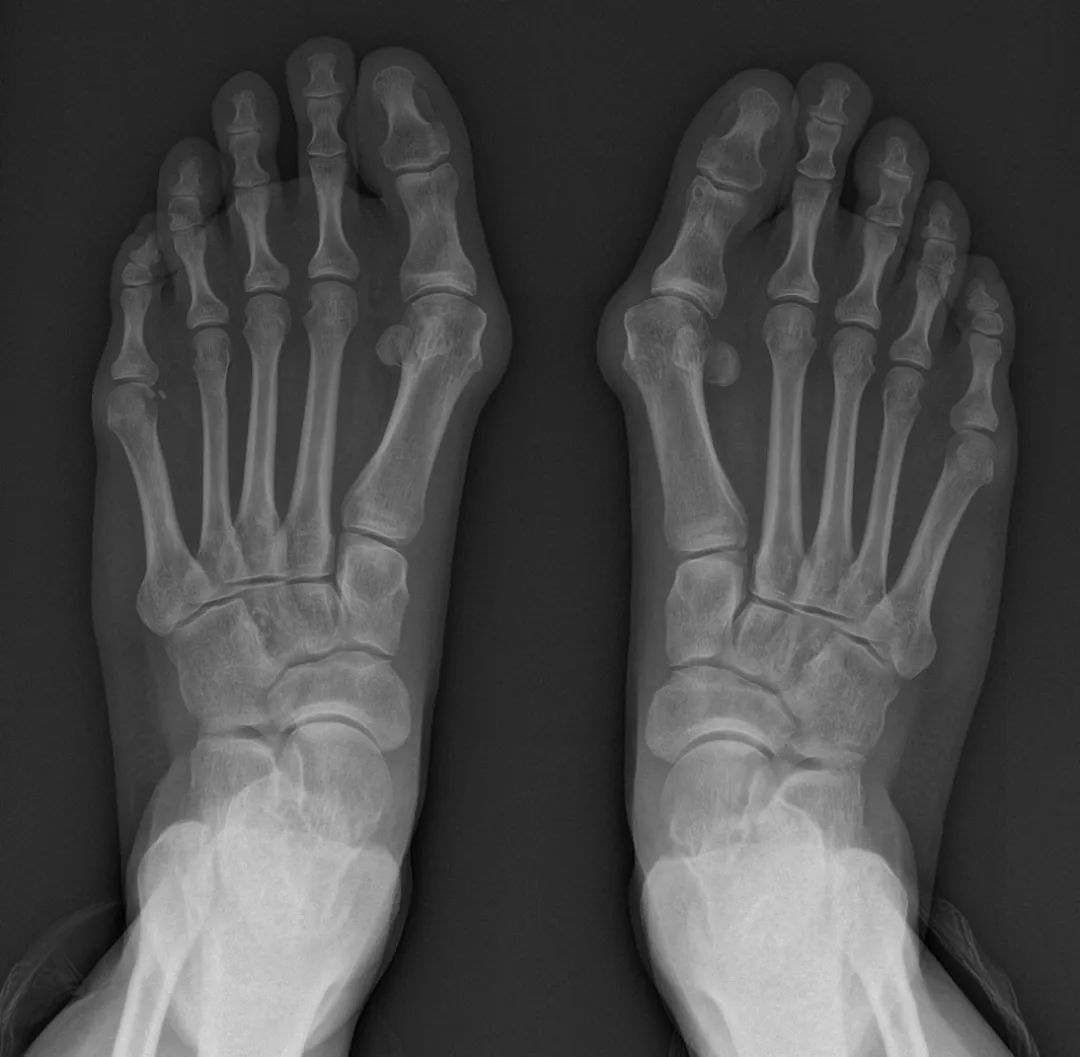

最后来到了江门市中心医院四肢关节骨科与运动医学科门诊,找到了运动医学与足踝外科亚专科马滚韶主任。通过详细的检查、AOFAS(前足)评分:20/100,FFI:146/230。负重行走时VAS评分2分。建议杜大姐进行手术治疗。

术前进行畸形角度的测量,制定确切的方案。

检查完善后明确了Mcbride+Scarf+Akin术